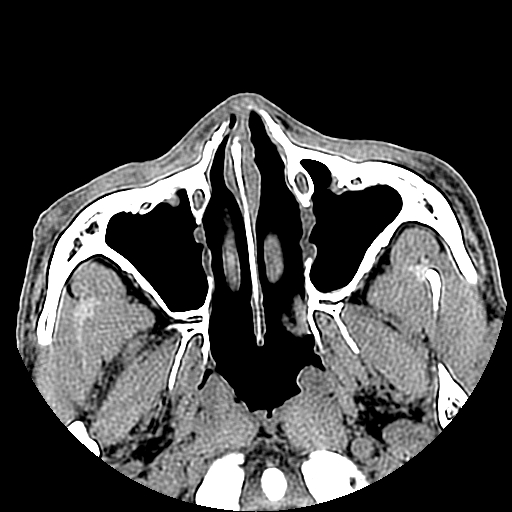

以下是引用liaoqiang在2008-7-16 21:15:00的发言:[br]右侧鼻骨骨折

以下是引用zxd95在2008-7-16 21:39:00的发言:[br]右侧上颌骨额突骨折。[br][br][br][br]